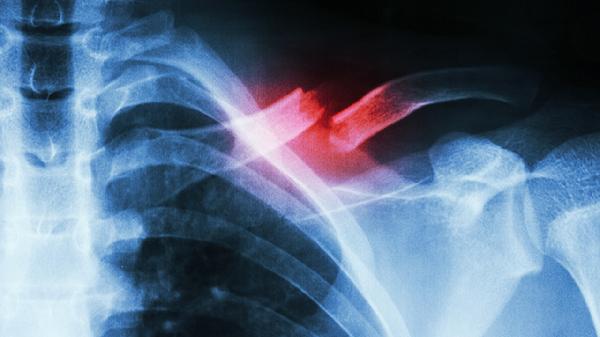

肋骨骨折是常见的胸部损伤,通常由外伤、摔倒或直接撞击引起。骨折后,患者会感到剧烈疼痛,尤其是在呼吸、咳嗽或活动时。对于是否适合坐飞机,需要考虑以下因素:

1、飞行气压影响:飞机在高空飞行时,机舱内气压会降低,可能导致胸腔内压力变化,引起疼痛或不适。肋骨骨折后,胸腔功能的恢复尚未稳定,气压变化可能加重症状。